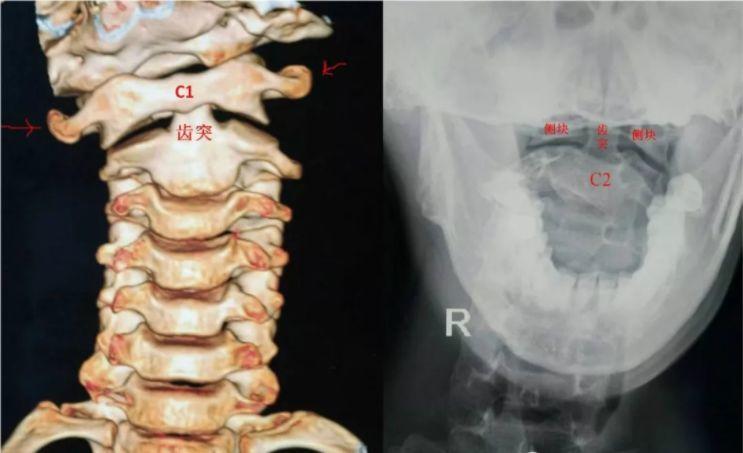

儿童寰枢椎半脱位

儿童寰枢椎半脱位,寰枢椎半脱位牵引图片

儿童寰枢关节半脱位的诊治

寰枢椎半脱位康复案例

小儿寰枢椎半脱位,你了解吗?

寰枢椎半脱位

儿童寰枢椎半脱位图片

寰枢椎脱位图

儿童寰枢椎不对称图

寰枢关节脱位图片

寰椎和枢椎图片

寰椎和枢椎解剖图

寰枢椎

寰枢椎正常图

寰枢椎解剖图

寰枢椎解剖